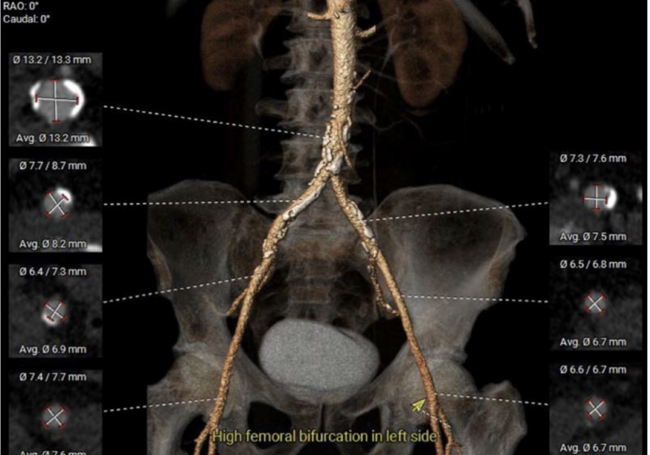

A 74-year-old man with severe aortic stenosis was prepared for a transcatheter aortic valve replacement. Main access was taken from the right femoral artery, as the left femoral artery had high bifurcation (Figure 1).